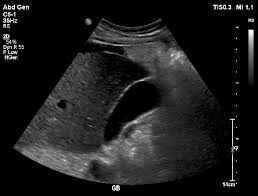

УЗИ желчного пузыря в Томске — современный метод диагностики

Здоровье органов пищеварения напрямую связано с качеством нашей жизни. Одним из ключевых элементов этой системы является желчный пузырь, который отвечает за накопление и выделение желчи, необходимой для переваривания жиров. Чтобы вовремя выявить нарушения в его работе, врачи часто назначают УЗИ желчного пузыря — простой, безопасный и информативный метод исследования.

Стандартное УЗИ проводится лёжа на кушетке. Врач наносит специальный гель и с помощью датчика осматривает пузырь, его форму, размеры и содержимое.

Что показывает УЗИ желчного пузыря?

Исследование помогает выявить:

●     камни и песок — видны даже мелкие образования;

●     дискинезию — нарушение моторики;

●     хронический или острый холецистит;

●     кисты, полипы и новообразования.